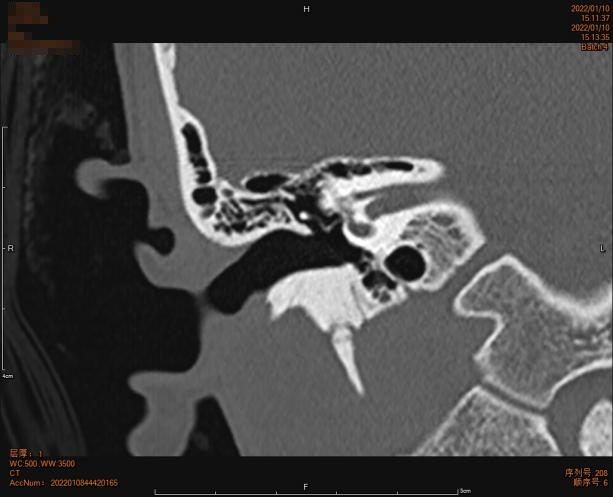

术后检查及随访:

出院日查房,患者无诉耳痛,无眩晕无面瘫等不适。查体:右耳伤口敷料固定,无渗血、渗液,双侧鼻唇沟对称,双眼闭目良好。音叉试验:右耳林纳试验(—),韦伯偏左。

患者术后恢复可,准予今日出院。

图片